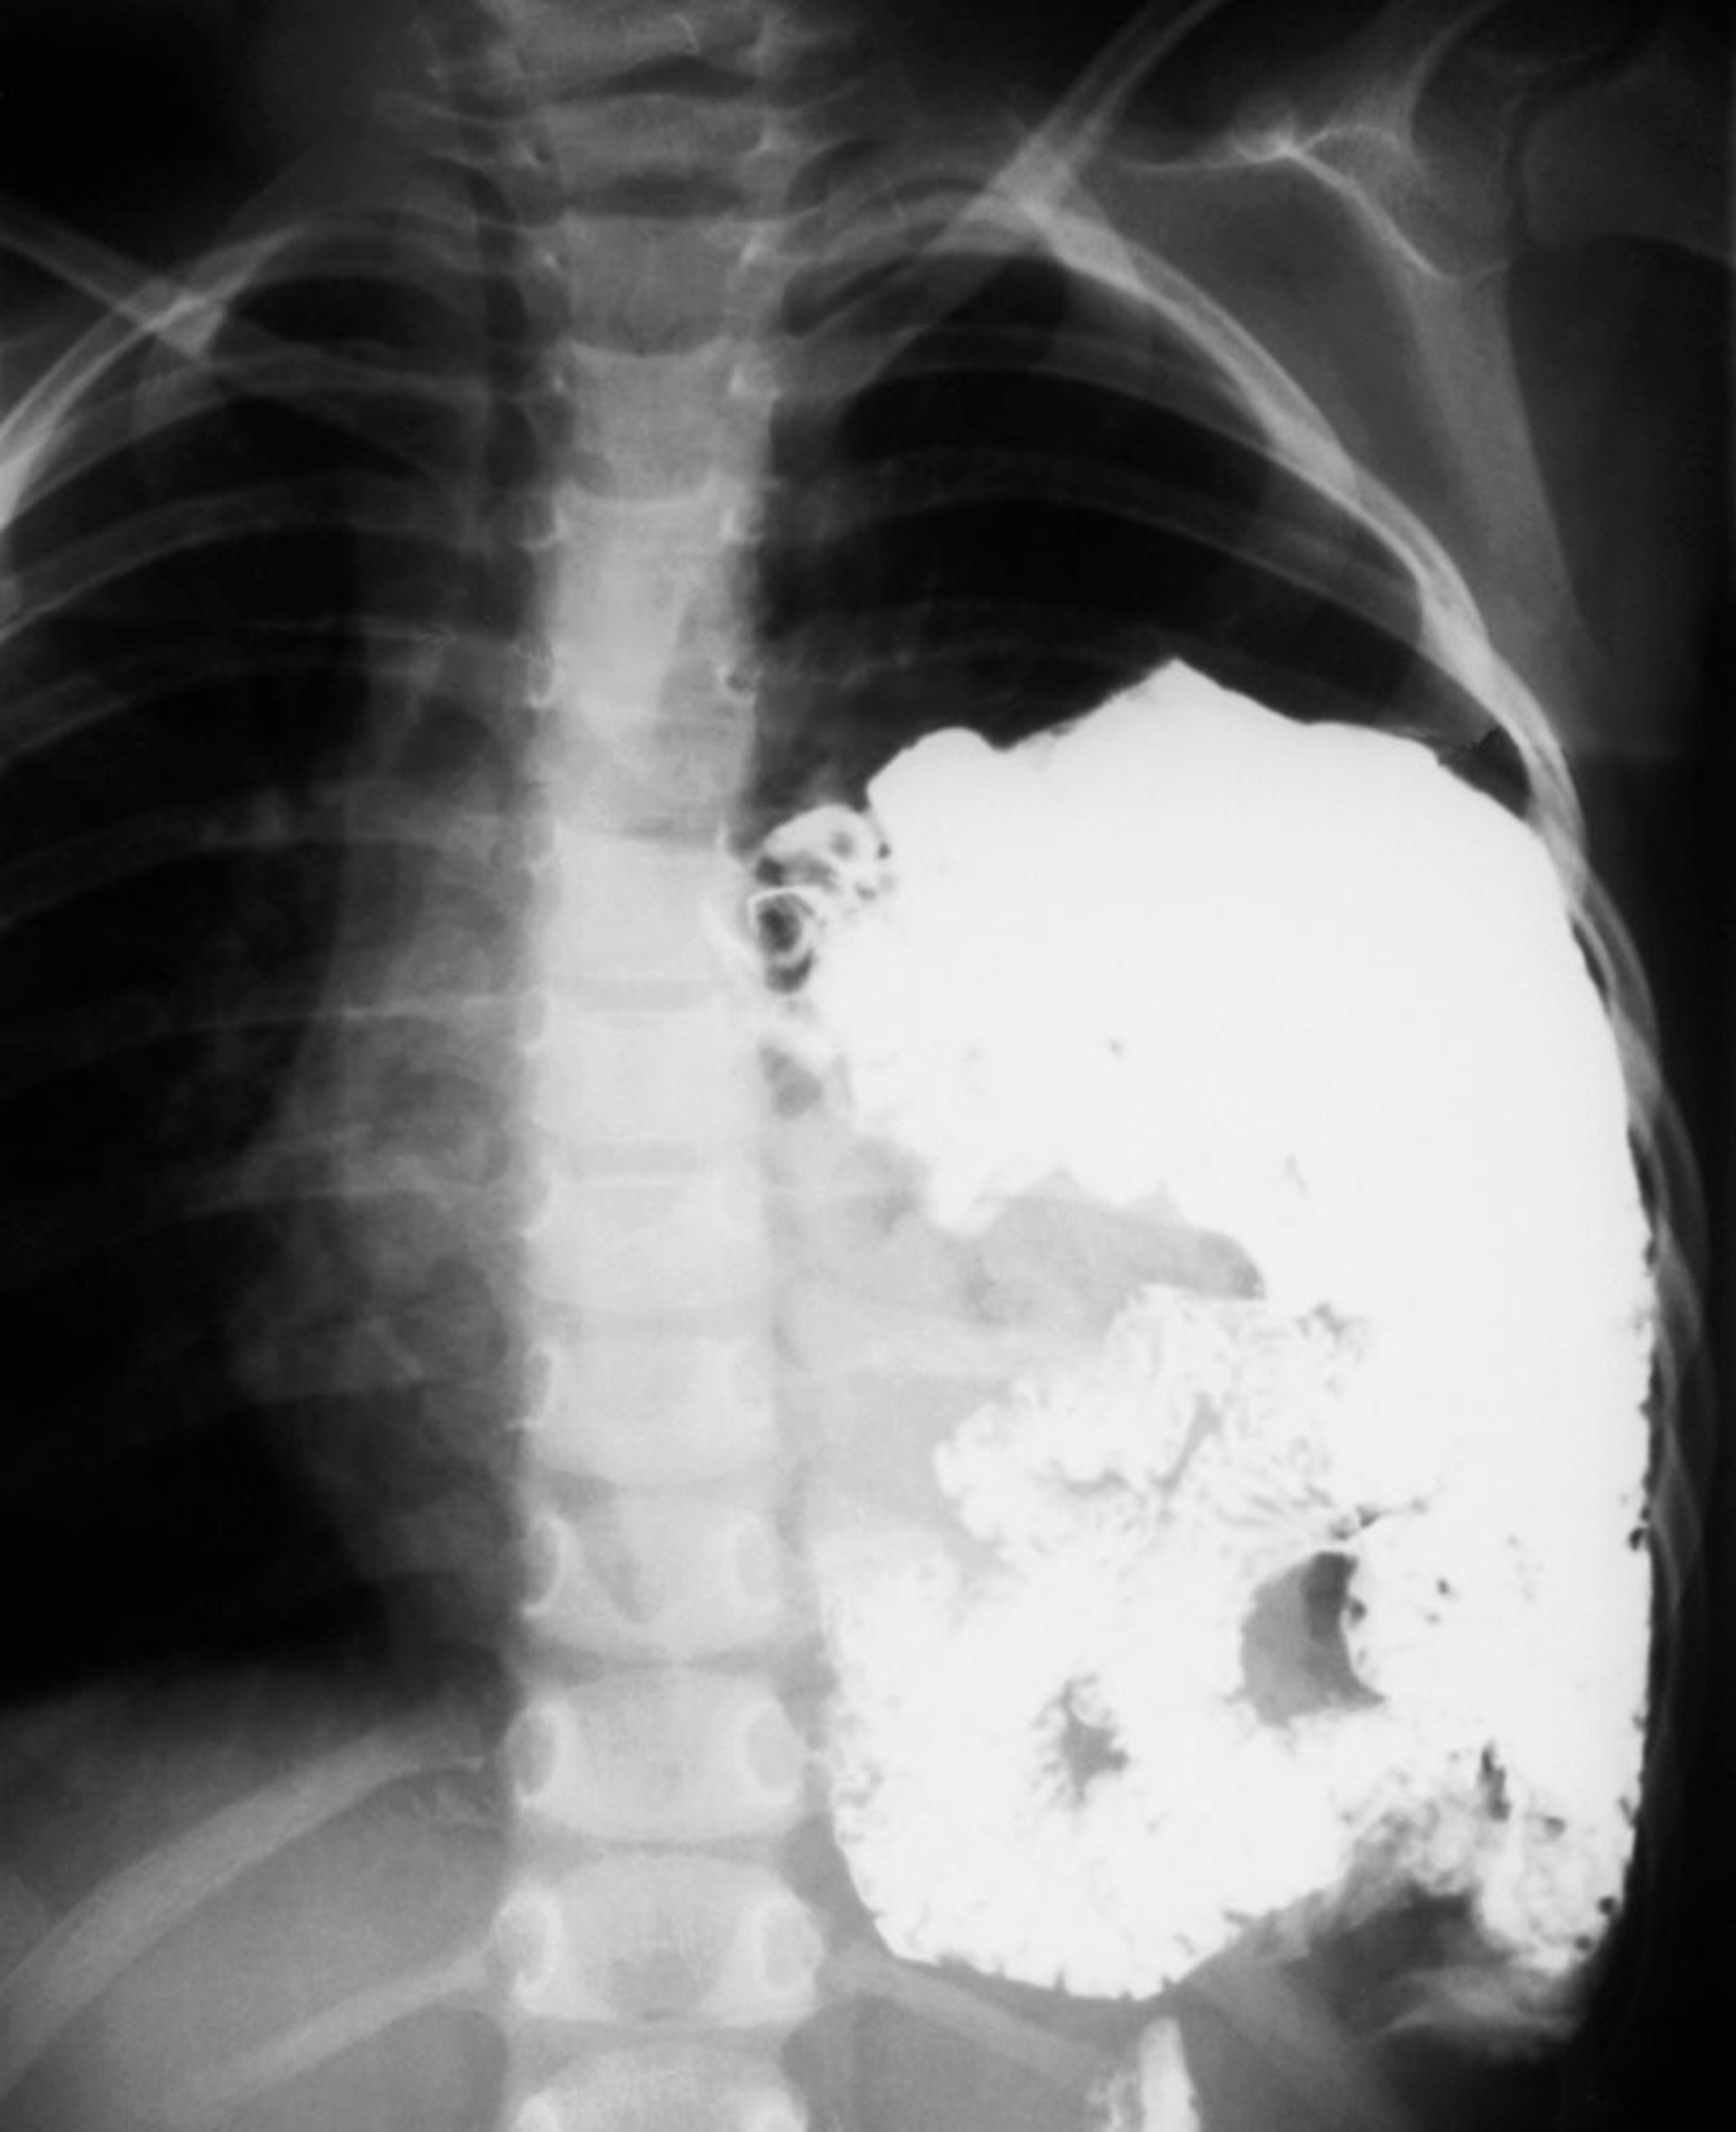

In this contrast study, stomach and bowel are seen in the left chest.

ZEPHYR/SCIENCE PHOTO LIBRARY